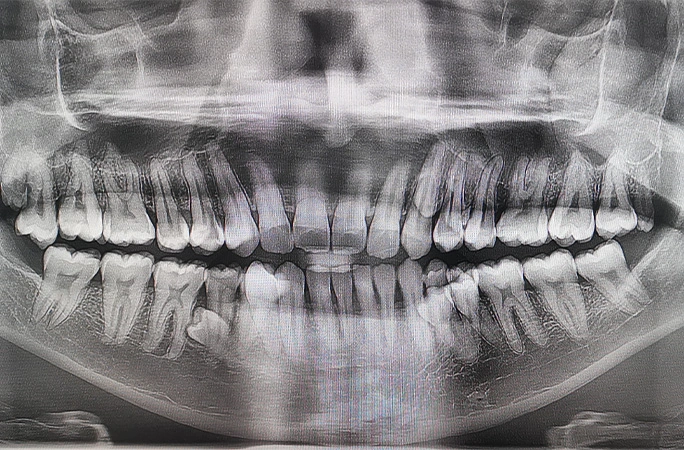

Lent.az xarici mediaya istinadən xbər verir ki, Ginnesin Rekordlar Kitabına görə, kişinin 42 dişi var ki, bu da orta statistik insandan on diş çoxdur və bu da ona kişilər arasında ən çox dişə görə dünya rekordu müəyyənləşdirməyə imkan verir.

Pratabın sözlərinə görə, o zaman ailəsi ilə zarafat edib ki, əlavə dişləri var. Birlikdə onları saymağa qərar veriblər və 38-ni müəyyən ediblər. Sonradan rentgen müayinəsi çənədə o vaxt çıxmamış daha dörd dişin olduğunu göstərib.

2023-cü ilin əvvəlində, diş müayinəsindən sonra kişinin ümumi diş sayının rəsmi olaraq 42 olduğu təsdiqlənib. Üstəlik, həkimlərin sözlərinə görə, onların əksəriyyəti bərabər böyüyür və heç bir ağırlaşma yaratmır.